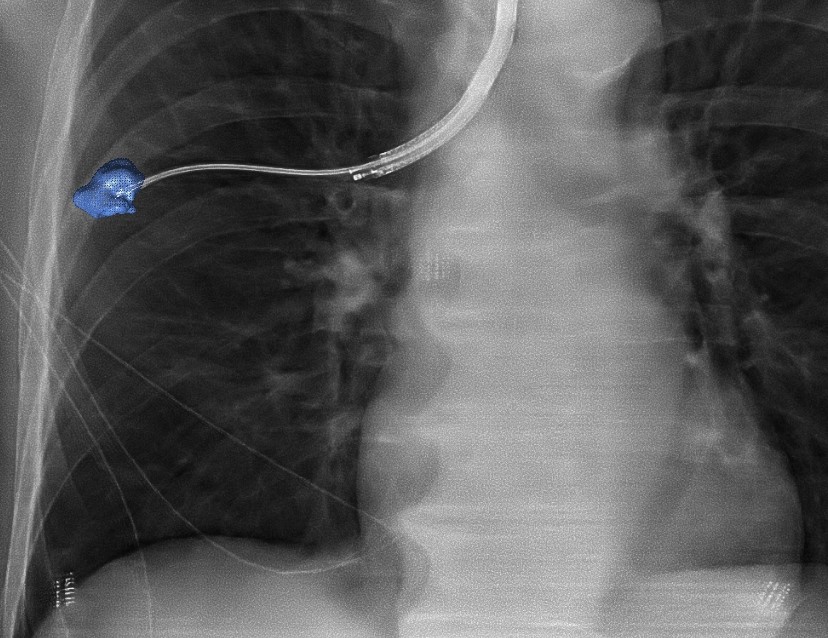

Radboudumc’s observational study reported the diagnostic accuracy and procedural radiation dose for patients undergoing an endobronchial lung biopsy supported by Philips Lung Suite - a solution that uses 3D imaging with augmented fluoroscopy to support high precision diagnosis and minimally-invasive therapy in one room. Diagnostic accuracy of 90% was reported while reducing the average total effective radiation dose per procedure by more than half from 47.5 Gy·cm2 (effective dose: 14.3 mSv) to 25.4 Gy·cm2 (effective dose: 5.8 mSv). The median long-axis diameter of the 248 lesions navigated to during the study was 13 mm (range 5-65mm). The results of the study were published in the October 2021 issue of the Journal of Bronchology & Interventional Pulmonology: Volume 28 - Issue 4 [1].

“The airways and lungs are very challenging places to biopsy, so we need good navigation to make sure we reach the target location,” said Dr. Erik van der Heijden, Pulmonologist and Associate Professor of Interventional Pulmonary Diseases at Radboudumc, who led the study. “Philips’ 3D imaging solution allows us to create real-time 3D visualizations enabling us to follow the correct path from different angles to where we need to be, which is particularly useful for very small abnormalities. Our study confirmed that it increases the accuracy and safety of the biopsy procedure, improving results for patients. Philips’ technology also offers the promising outlook that we could not only diagnose but also immediately treat these early-stage patients using novel procedures such as tumor ablation.”

A new method is image-guided endobronchial lung biopsy, during which a clinician uses live image guidance to maneuver through the airways in the lungs to advance a catheter towards the lesion. However, the airways in the lungs are a complex network that requires accurate navigation to remove the required tissue sample. Until now, image-guided endobronchial lung biopsy has only really been effective when an abnormality or tumor is located in or near one of the larger airways in the lungs, and even then it is challenging for clinicians to accurately navigate when looking at a 2D greyscale fluoroscopy image while the lungs are moving as the patient breathes.

Philips Lung Suite enables all-in-one lung cancer diagnosis and treatment. It provides advanced real-time 3D imaging with augmented fluoroscopy on the company’s Image Guided Therapy System – Azurion, combined with dedicated software. With Philips’ Cone Beam CT imaging, the X-ray detector rotates around the patient to generate a CT-like image in around five seconds, providing clinicians with a high-resolution 3D view of the target lesion and other anatomical structures. This allows the clinician performing the biopsy procedure to be continually guided by high-quality real-time imaging to advance a catheter towards the lesion through a bronchoscope. Once done, its position can be confirmed in real-time using the same imaging modality and a biopsy sample removed.